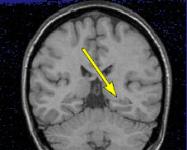

Fig.1 Fig.2 Fig.3

MRI FINDINGS: MRI detects mesial temporal sclerosis by demonstrating size asymmetry and abnormal signal within the atrophied hippocampus. Thin-section, high-resolution oblique coronal MR images are best for detecting these abnormalities, which can be subtle. Heavily T1-weighted images (Fig. 1) are best for detecting size asymmetry of the hippocampal gyri, while T2-weighted images (Fig. 3) and particularly FLAIR (fluid attenuated inversion recovery) images are most sensitive for detecting signal abnormalities (Fig. 2). The above images demonstrate left hippocampal atrophy and mesial temporal sclerosis (arrows).